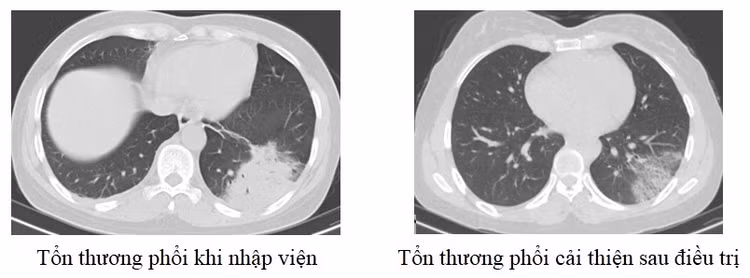

Mới đây nhất là trường hợp người bệnh nữ 48 tuổi, địa chỉ ở Lập Thạch, Vĩnh Phúc vào viện vì ho khạc đờm, sốt cao. Xét nghiệm máu cho thấy chỉ số viêm tăng cao, chụp phổi ghi nhận đông đặc diện rộng phổi trái. Người bệnh được điều trị tích cực và ra viện sau 1 tuần điều trị.

| Tổn thương phổi trên phim chụp của bệnh nhân 48 tuổi - Ảnh BVCC |